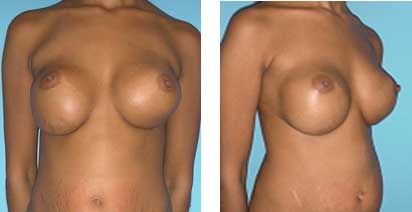

This patient had a breast augmentation by a non-plastic surgeon after her pregnancy using implants in a subglandular plane.

The correct procedure would have been to combine a breast augmentation with a breast lift.